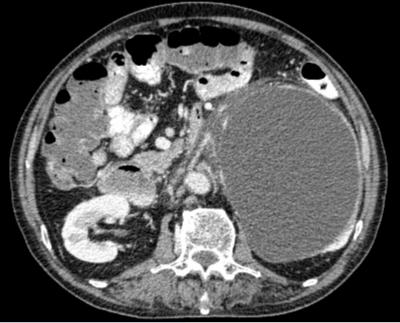

abdominal mass with haematuria

Article |

June 28, 2019 - 12:26pm

| By

HAYATI F

,

AZIZAN N

CHONG TH

NIK AMIN S

ZAINAL ABIDIN ZA

Related Terms:

-

Quiz